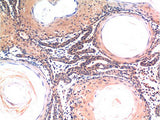

Applications IHC-p

IHC 1:100-200